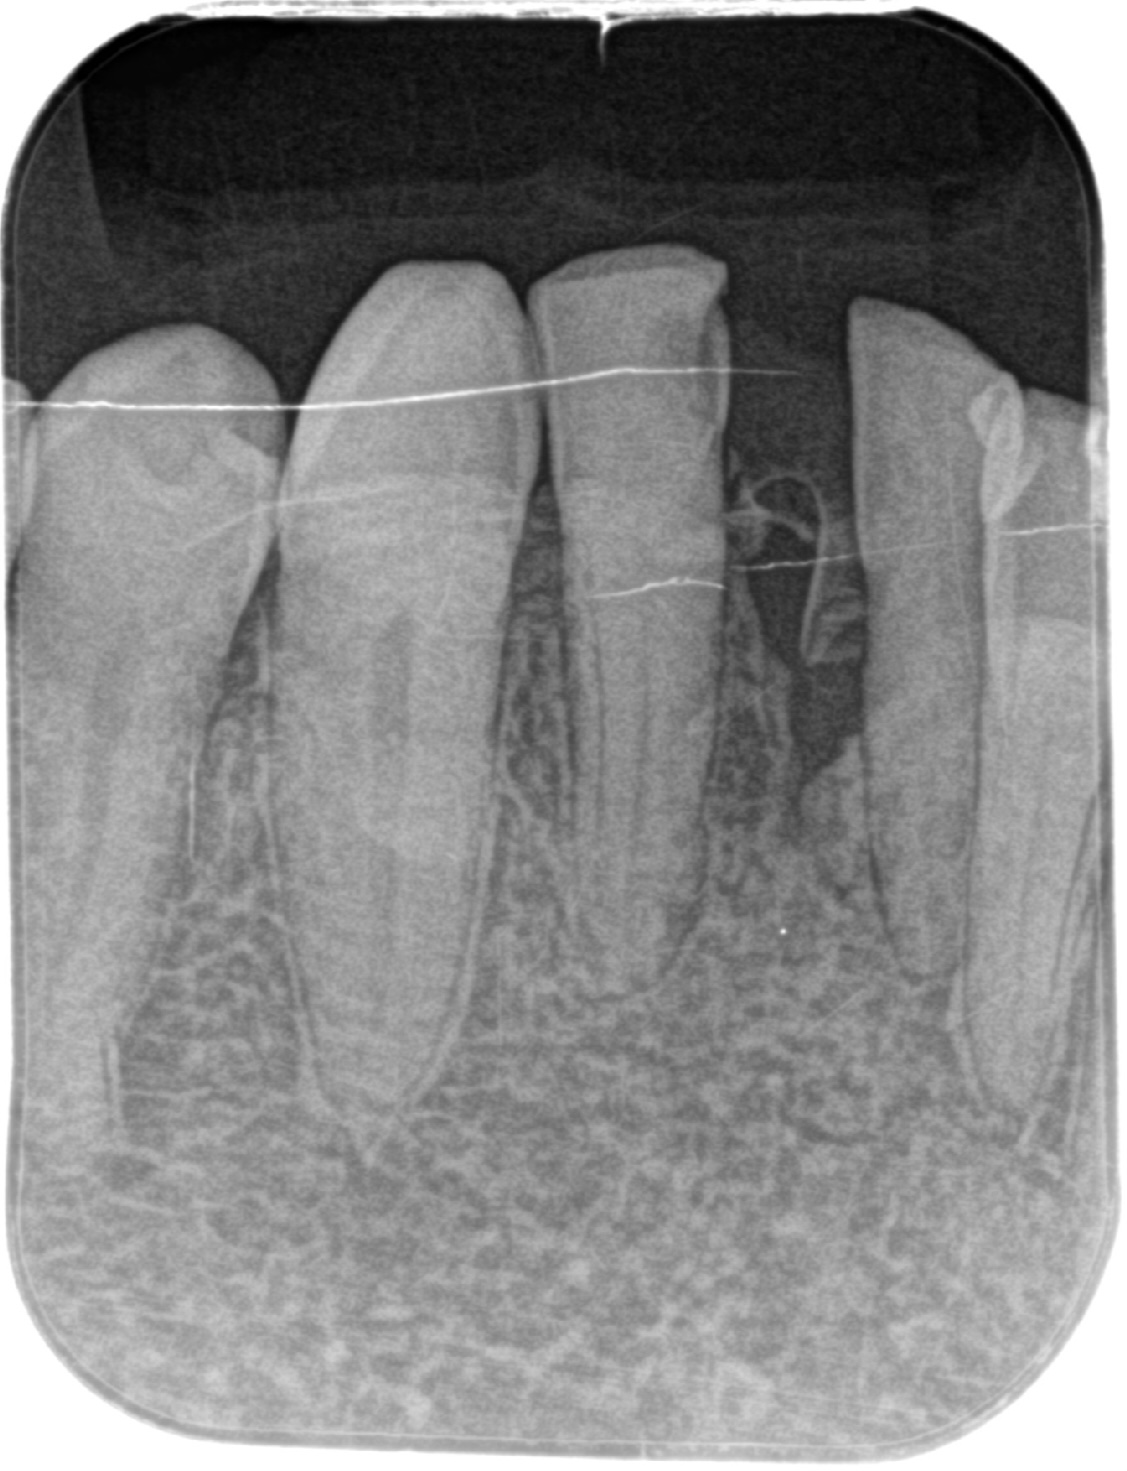

世界でも数多くの歯科医師に選ばれている「ストローマンインプラント」を採用。先進設備による精密な検査・診断と丁寧な処置で、埋入手術による痛みや腫れを減らし、安定性の高い長持ちするインプラント治療を提供しています。